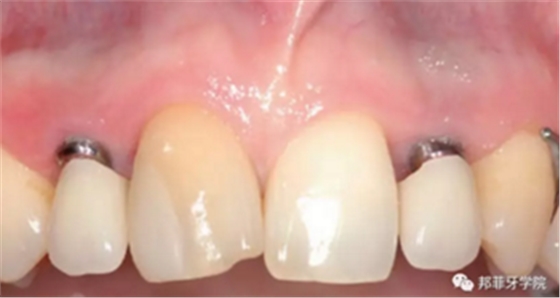

26歲女性患者,雙側上頜側切牙先天缺失,對原有修復體的“形態(tài)”、“光澤”等方面不滿意,希望重新修復(圖1&2)。12及22原為粘接橋修復,11根管治療史;拆除原修復體后余鄰牙完整,未見病理性探診深度。無系統(tǒng)疾病史?;颊咂谕递^高,告知治療流程佩戴臨時卡環(huán)義齒等(圖3)、費用、風險后表示接受治療。

圖1:治療前口內情況

最終印模采用個性化印模柱,記錄穿齦輪廓(圖13)。CAD/CAM個性化基臺精確就位(圖14)。全瓷冠水門汀固位(圖15)。